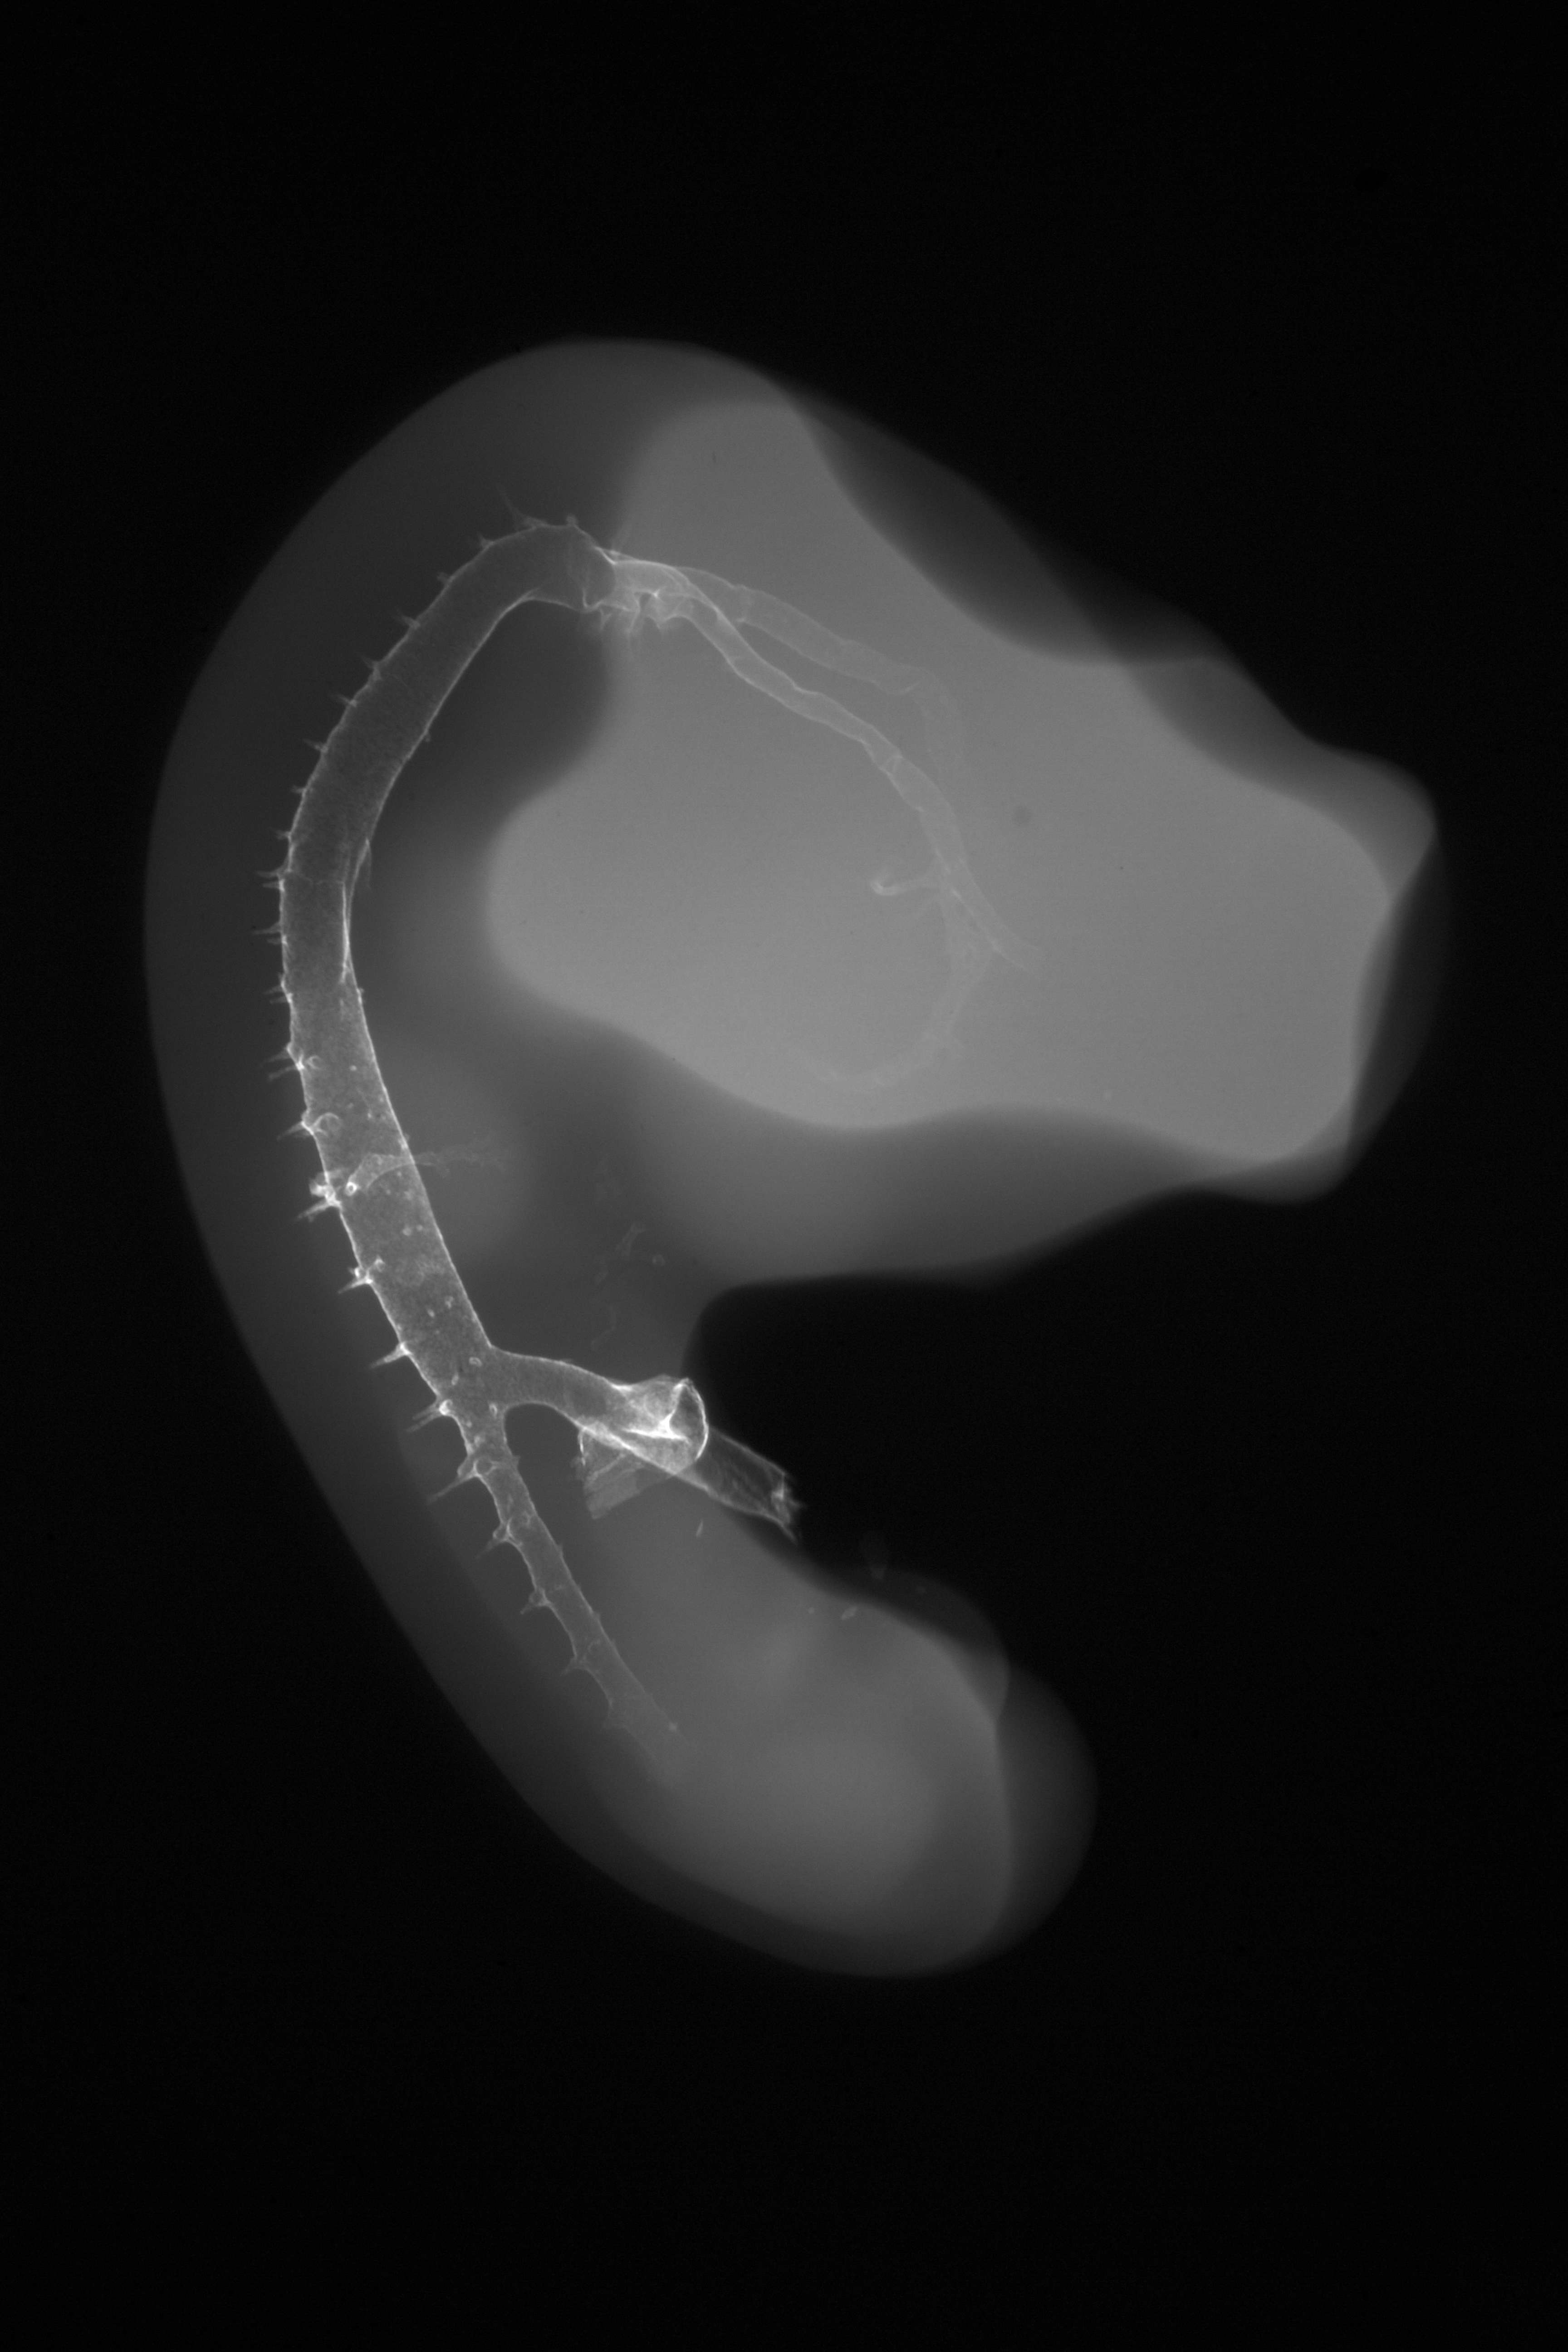

Hamburger-Hamilton (HH) Stage 23 (approx. 4 days)

X-Ray Micrographs